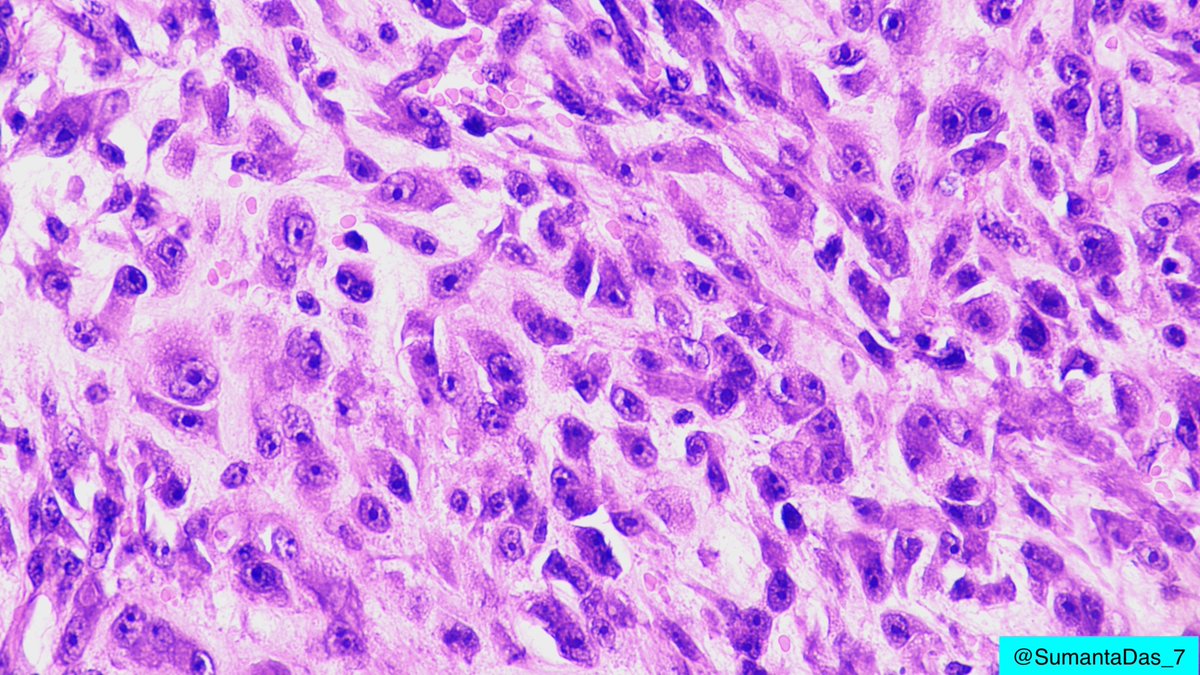

Male in 40s. Forearm mass. On low magnification, hypercellular area and hypocellular loose myxoid areas. On high magnification, sheets of ganglion-like cells with amphophilic cytoplasm, vesicular nuclei and prominent nucleoli. #PathTwitter #BSTpath

1

24

54